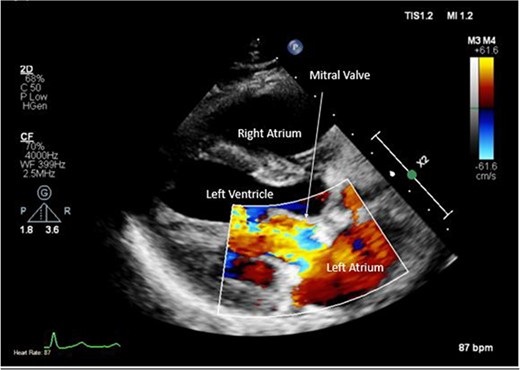

Pre-operative TTE with Doppler depicting mitral valve with vegetation (labelled).

Intra-operatively, femoral–femoral bypass was established and a 3 cm windsock vegetation was found with a 1.5 × 1.5 cm hole at the aortic inlet on the annular junction. The vegetation travelled from the LV to LA as shown in Figs 3 and 4. The vegetation was excised and the valve debrided, which resulted in moderate regurgitation from severe. Hence, a further 26 mm Physio II ring was placed resulting in no mitral regurgitation. The excised vegetation is shown in Fig. 5 and the post-op TTE images are shown in Figs 6 and 7.